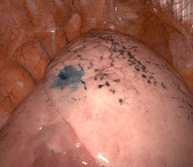

Cette technique nécessite un fibroscope bronchique, c’est-à-dire une caméra miniaturisée permettant d’explorer le poumon et les bronches de l’intérieur, par les voies naturelles.

La minisonde est une sonde de 2 mm qui s’insère dans le fibroscope permettant compte tenu de sa petite taille d’ aller plus loin dans les bronches de petit calibre. Cette minisonde est elle-même équipée d’une sonde d’échographie, miniaturisée à l’extrême, permettant d’examiner le poumon de l’intérieur.

Ainsi des cancers à des stades plus précoces qu’auparavant peuvent être repérés et opérés.